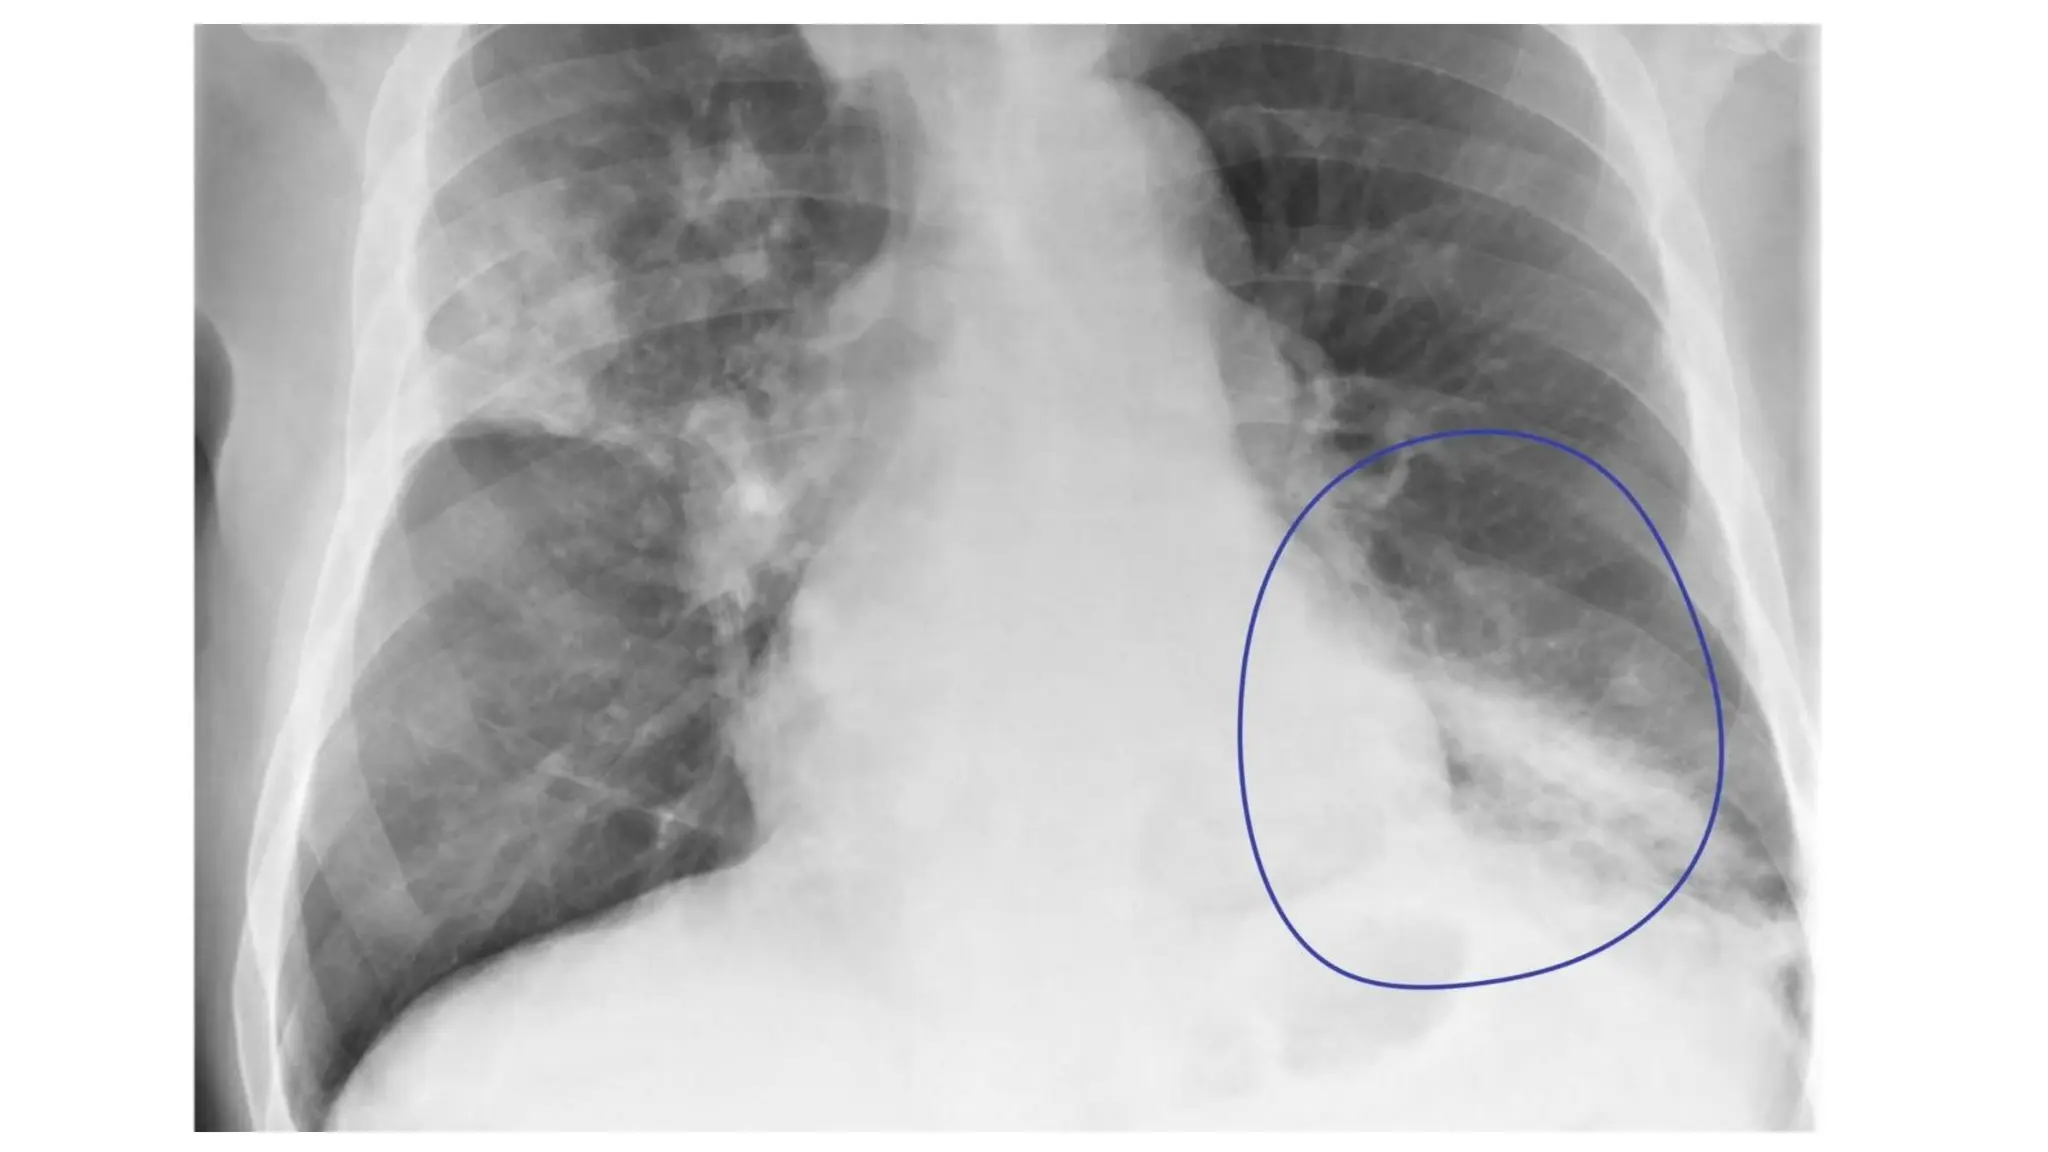

Costophrenic angles

• The costophrenic angles reflect the dome

shape of hemidiaphragm as it meets the

lateral chest wall.

• The loss of this angle is termed as

costophrenic blunting & causes

includes:

Pleural effusion

Consolidation

Hyperinflation (e.g. asthma copd)

Costophrenic angles • Thecostophrenic angles reflect the dome shape of hemidiaphragm as it meets the lateral chest wall.

• 57.

• The lossof this angle is termed as costophrenic blunting & causes includes: Pleural effusion Consolidation Hyperinflation (e.g. asthma copd)